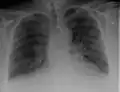

Chest radiograph of a lung with distinct Kerley B lines, as well as an enlarged heart (as shown by an increased cardiothoracic ratio, cephalization of pulmonary veins, and minor pleural effusion as seen for example in the right horizontal fissure. Yet, no obvious lung edema is seen. Overall, this indicates intermediate severity (stage II) heart failure.

Chest X-rays are frequently used to aid in the diagnosis of CHF. In a person who is compensated, this may show cardiomegaly (visible enlargement of the heart), quantified as the cardiothoracic ratio (proportion of the heart size to the chest). In left ventricular failure, evidence may exist of vascular redistribution (upper lobe blood diversion or cephalization), Kerley lines, cuffing of the areas around the bronchi, and interstitial edema. Ultrasound of the lung may also be able to detect Kerley lines.[72]